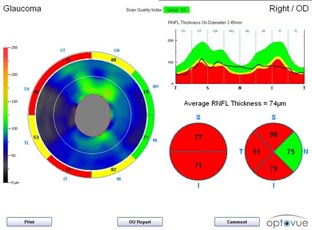

Současné zobrazovací metody glaukomu považujeme za velmi přínosné pro stanovení diagnózy glaukomu a sledování vývoje onemocnění v čase. Těmito metodami sledujeme objektivně projevy glaukomové neuropatie včetně její progrese.